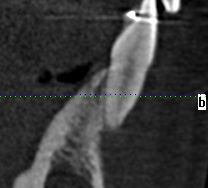

Der Patientin wurde eine adäquate Mundhygiene insbesondere bei der Rezession am Zahn 32 gezeigt. Bei der radiologischen Abklärung zeigte sich bei den 2-dimensionalen Bildern noch genügend Alveolarknochen interdental (Abb. 4 und 5). Beim DVT hingegen sieht man die Verlagerung der Zähne nach bukkal aus dem Knochen hinaus (Abb. 6 und  7). Der Zahn 33 wurde mit Composite verlängert, um eine Eckzahnführung zu etablieren und die Belastung vom Zahn 32 zu reduzieren.

Anschliessend wurden die Wurzelspitzen kieferorthopädisch unter DVT-Kontrolle wieder in den Knochen hineinbewegt sowie der Eckzahn aufgerichtet (Abb. 9).